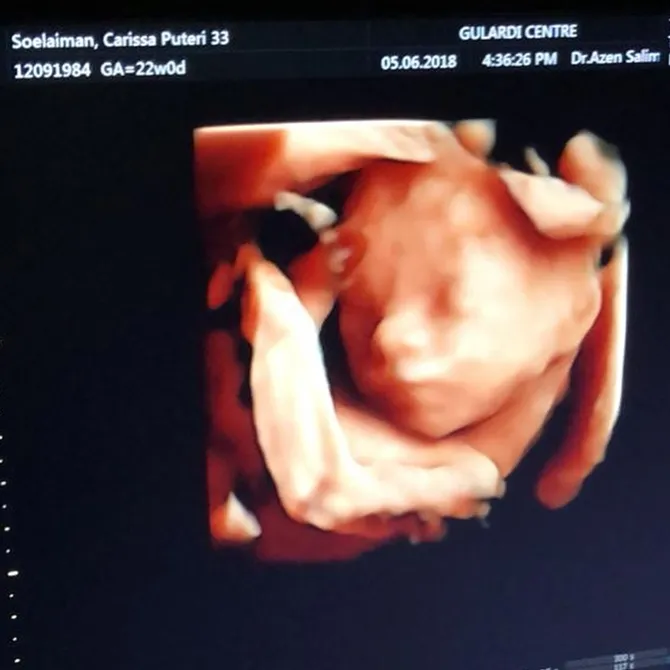

3. Hamil 33 minggu

Kini kandungan Carissa Puteri telah semakin besar. Tepatnya 33 minggu. Dengan kata lain tak lama lagi Q akan bertemu dengan sang adik, yeay!

Di usia kandungannya ini Carissa Puteri memposting foto dirinya dan juga Q. Pada foto itu terlihat kalau ibu dan anak ini sedang berada di sebuah klinik. Dengan senyum manis, keduanya berpose.

Carissa juga mengungkapkan sebuah harapan untuk Q yang ia tulis pada kolom caption. Katanya, "Q selalu nemenin mama cek ke Dokter.. Semoga jd kakak yg selalu sayang & jagain adenya.. Thank you Q." Amin... sayang sama adik ya, Q!